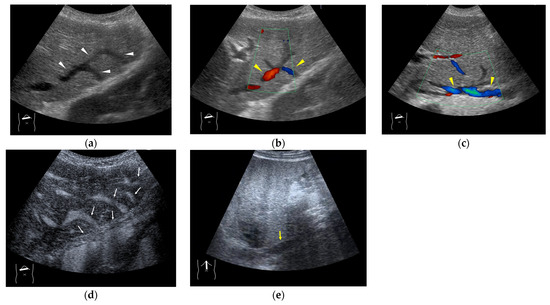

4.4. Hemodynamic Abnormalities in Liver Abscess

4.5. Hemodynamic Abnormalities in Liver Necrosis

4.6. Hemodynamic Abnormalities in Acute Cholecystitis